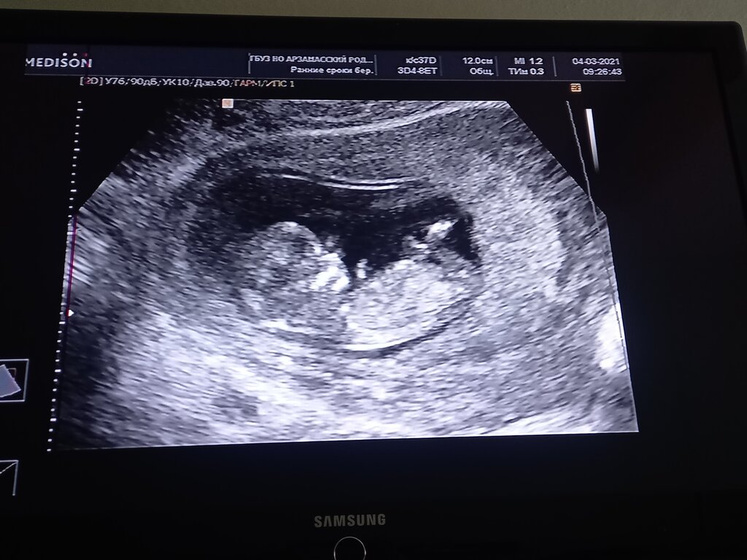

Сегодня был первый скрининг, я так переживала и волновалась, когда легла на кушетку и начали делать УЗИ увидела малыша??? он такой большой уже как мне показалось ? видела носик, ножки, ручки слышала сердечко ? а ещё шевелил левой ручкой ? как будто махал привет мама и папа? у меня все хорошо ?чуть не расплакалась от счастья ?? в общем все хорошо, как сказал врач для 12 недель все очень хорошо, и у меня все отлегло ? пол конечно ещё не говорили, да и я понимаю так как срок маленький ещё ?